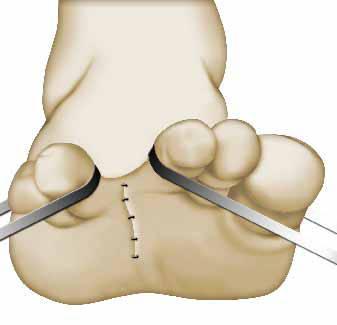

Συρραφή τομής

Ο χειρουργός επανατοποθετεί τα στοιχεία που μετατόπισε για την επέμβαση. Ο σύνδεσμος δεν χρειάζεται συρραφή, καθώς επουλώνεται μόνος του.

Είναι φυσιολογικό η εγχειρισμένη περιοχή να παράγει υγρά (αίμα, κτλ). Αν χρειαστεί, ο χειρουργός σας τοποθετεί ένα λεπτό σωληνάκι, (παροχέτευση), για να παροχετεύονται τα υγρά μετά την επέμβαση.

Για τη συρραφή της τομής, ο γιατρός σας χρησιμοποιεί ράμματα, ή κάποιο άλλο σύστημα συρραφής, που είναι σταθερό ή απορροφάται σταδιακά από τον οργανισμό (απορροφήσιμο υλικό).

Η τελική μορφή της ουλής εξαρτάται από την κατάσταση του δέρματός σας, τα «τραβήγματα» που υφίσταται, ή ακόμα από την έκθεσή σας στον ήλιο, που πρέπει να αποφεύγεται μετά την επέμβαση.